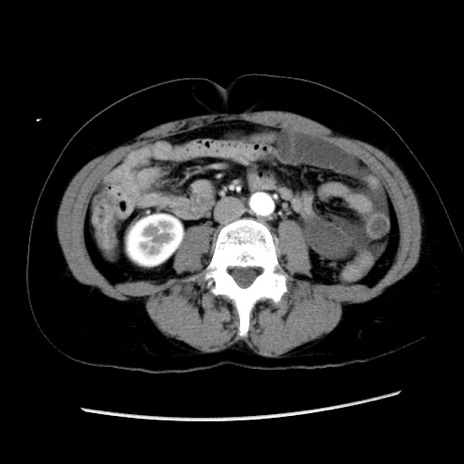

症例10(横断像)

【症例】 50歳代女性

【主訴】 腹痛

【現病歴】前日生レバーを食べた。今朝に排便あり。 昼前に突然発症の腹痛を生じ、当院救急外来を受診した。

【既往歴】 子宮筋腫にてで子宮全摘後

【身体所見】 意識清明、腹部:平坦、軟、下腹部やや左を中心に圧痛・反跳痛あり、筋性防御あり

【データ】WBC 7800、CRP 0.07